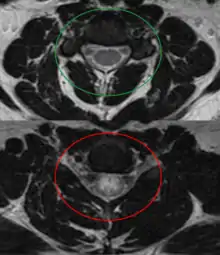

![]() | |

| An MRI showing a transverse myelitis lesion, which is lighter, oval shape at center-right. The patient recovered 3 months later. | |